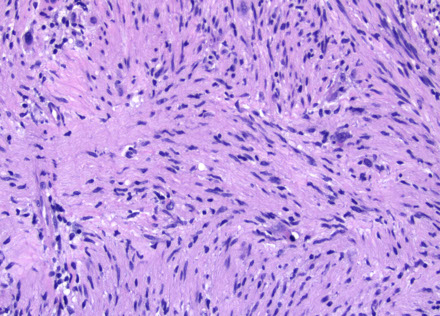

Hemangiopericytoma

May be mistaken for meningioma due to similar clinical and radiologic finding, and are thus treated c embolization followed by surgery

- tend to occur at younger ages than meningioma

- should suspect this in a spinal lesion in a younger male, even before frozen section

same as HPC in other parts of body, with characteristic staghorn vessels, abundant cellularity with ovoid appearance

- patternless pattern

Call it anaplastic if >5 mits/10 hpf or necrosis or bad nuclear atypia

IHC: Reticulin shows pericellular reticulin network; most have patchy CD34; and a caveat is that it can be EMA (+) --> just like meningiomas, (+) CD99

Px: may behave more poorly in CNS than elsewhere